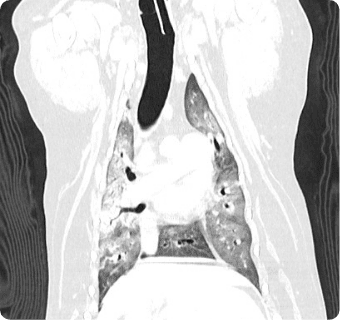

빠른 촬영속도를 통해 마취시간을 최소화 하며, 선명한 3차원 영상을 구현합니다.

종양, 전이평가, 선천적 혈관 기형 등 여러 질환의 조기 발견 및 환자상태를 평가합니다.

폐 실질 평가, 폐 염전, 폐 종양, 종격동 종양, 심장종양, 폐 전이 평가, 기관, 기관지, 식도의 평가, 복막심낭횡격막탈장, 동맥관개존증